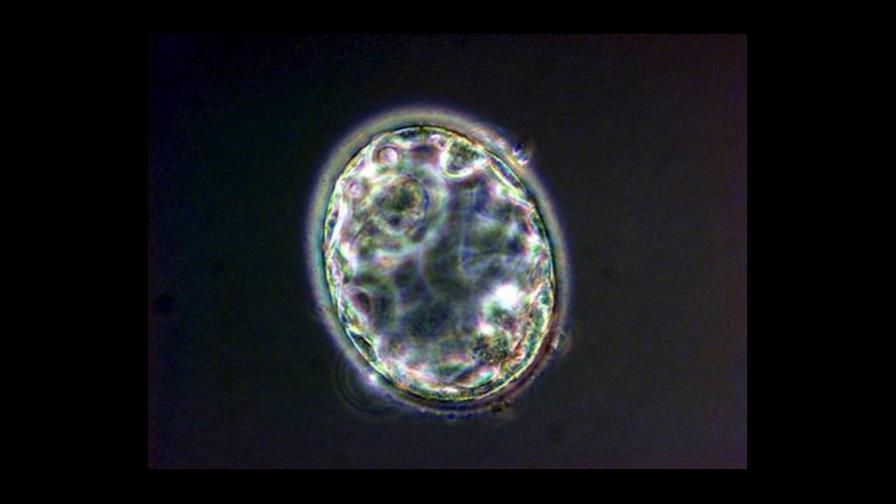

La técnica usada por Mitalipov y sus colaboradores es una variación de un método de uso común, llamado transferencia nuclear de célula somática que consiste en el trasplante del núcleo de una célula, que contiene el ácido desoxirribonucleico de un individuo, a un óvulo al cual se le ha retirado su material genético.

El óvulo no fertilizado se desarrolla y eventualmente produce células madre.

En el artículo de la revista Cell, Mitalipov señaló que "un examen detallado de las células madre derivadas mediante esta técnica demostró su capacidad de convertirse, al igual que las células madre normales de embrión, en varios tipos diferentes de células, incluidas las células nerviosas, del hígado y del corazón", indicó Mitalipov en el artículo.

La clave del éxito fue hallar una manera de hacer que los óvulos permanecieran en una etapa conocida como "metafase" durante la transferencia nuclear.

La metafase ocurre en el proceso natural de división celular, o meiosis, cuando el material genético se alinea en medio de la célula antes de que ésta se divida.

El equipo investigador encontró que el mantenimiento químico de la metafase durante todo el proceso de transferencia impedía que el proceso se atascara y permitía que las células se desarrollaran y produjeran células madre.